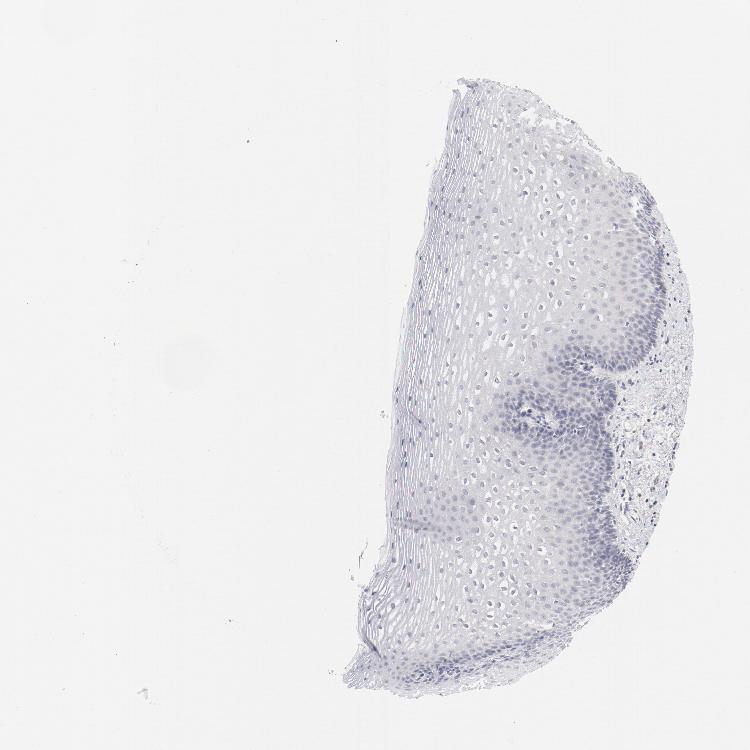

ESOPHAGUS - Antibody stainingi

Antibody staining in the annotated cell types in the current human tissue is reported as not detected, low, medium, or high, based on conventional immunohistochemistry profiling in selected tissues. This score is based on the combination of the staining intensity and fraction of stained cells.

Each image is clickable and will lead to virtual microscopy that enables deeper exploration of all samples and also displays staining intensity scores, fraction scores and subcellular localization as well as patient and tissue information for each sample.

Antibody CAB003685

Squamous epithelial cells Not detected